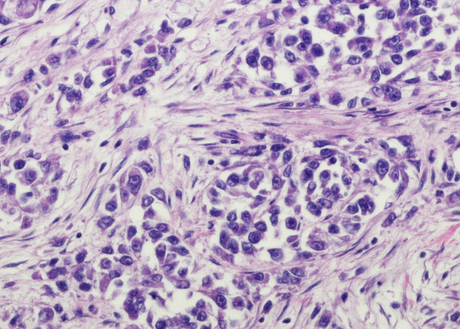

An image of chronic lymphocytic leukemia cells under a microscope